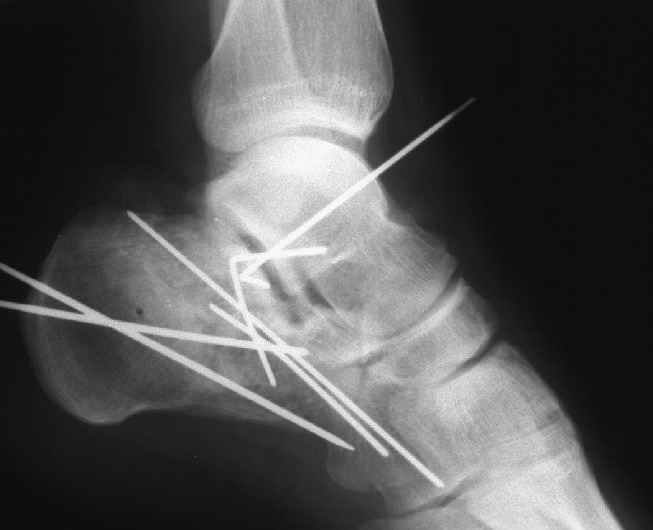

Окончательная фиксация спицами, пяточными пластинами (5) , в последнее время стали применять крючковидные пластины (ДЕОСТ) (6,6a).